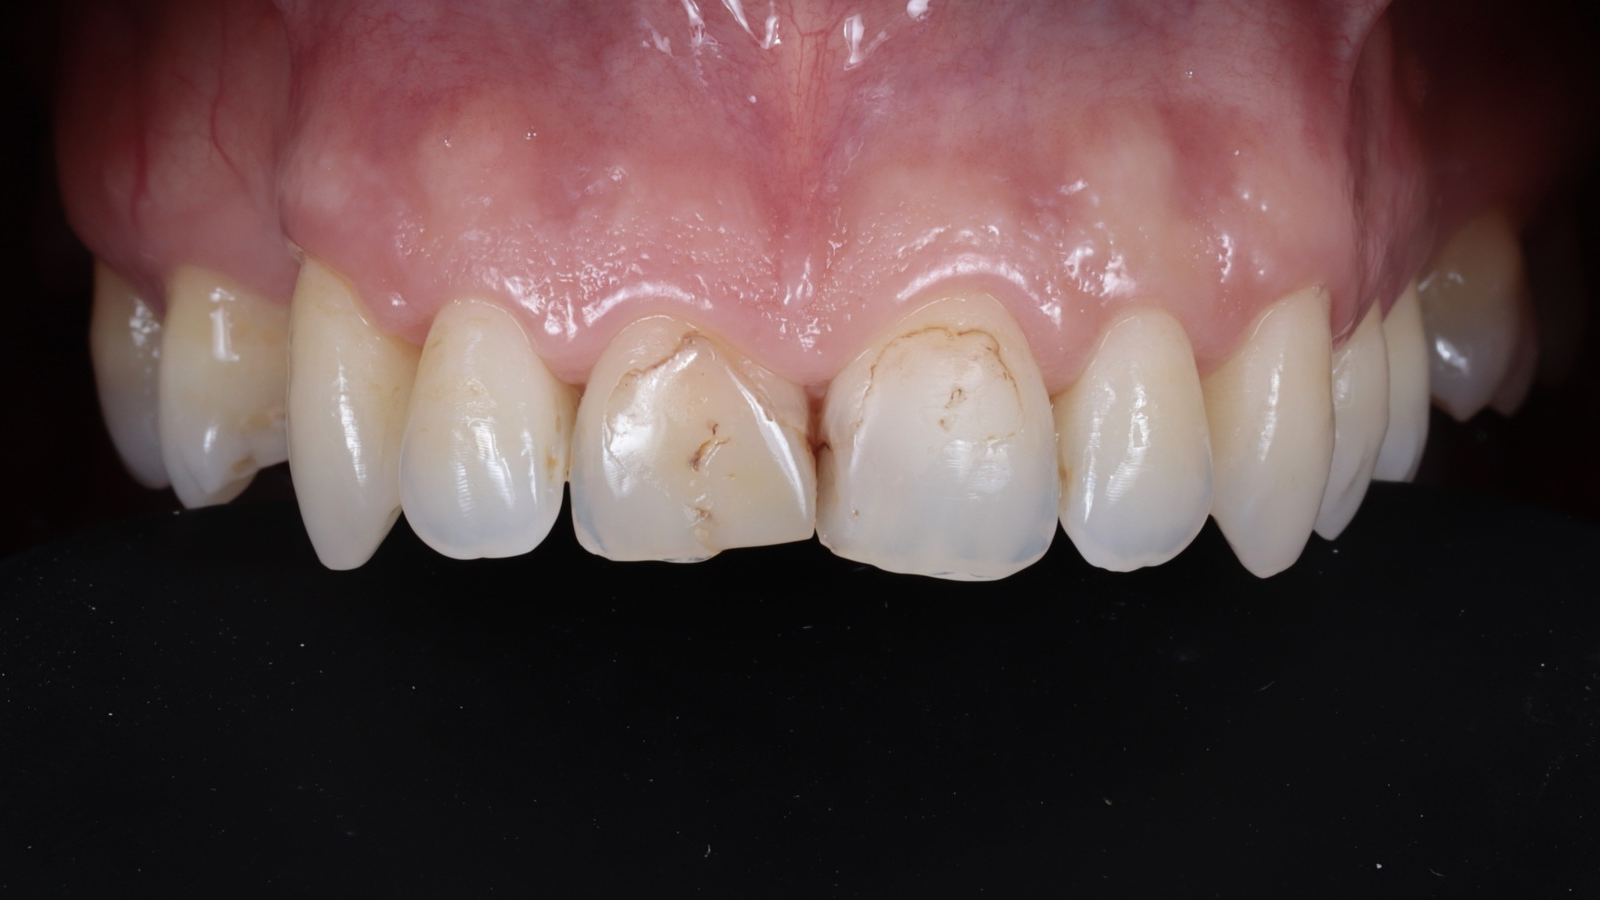

The dam was removed, and the finally polished restorations were revealed.

The restorations achieved complete integration with the natural tooth tissue after rehydration. The composite independently developed areas of translucency based on the thickness created, resulting in a highly aesthetic and natural appearance.